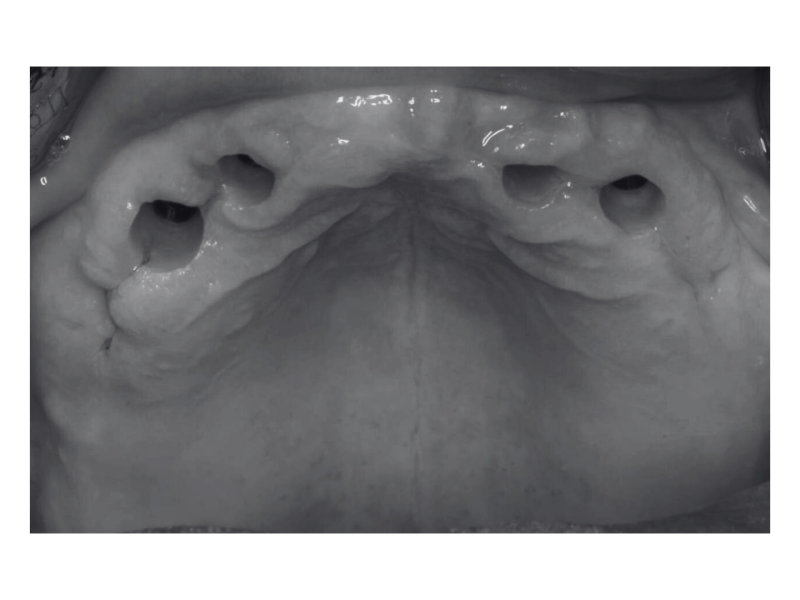

Имплантация All-on-4

Пациент обратился с жалобами на отсутствие нескольких зубов и желание восстановить жевательную функцию и эстетику улыбки. Проведена диагностика, анализ КТ и планирование хирургического этапа. Определены оптимальные позиции для установки имплантов с учётом анатомических особенностей. Установлены 4 импланта в один хирургический этап под местной анестезией. Даны рекомендации по уходу и назначен контрольный приём для оценки приживления

Доктор: Шарифуллин Айнур Азатович